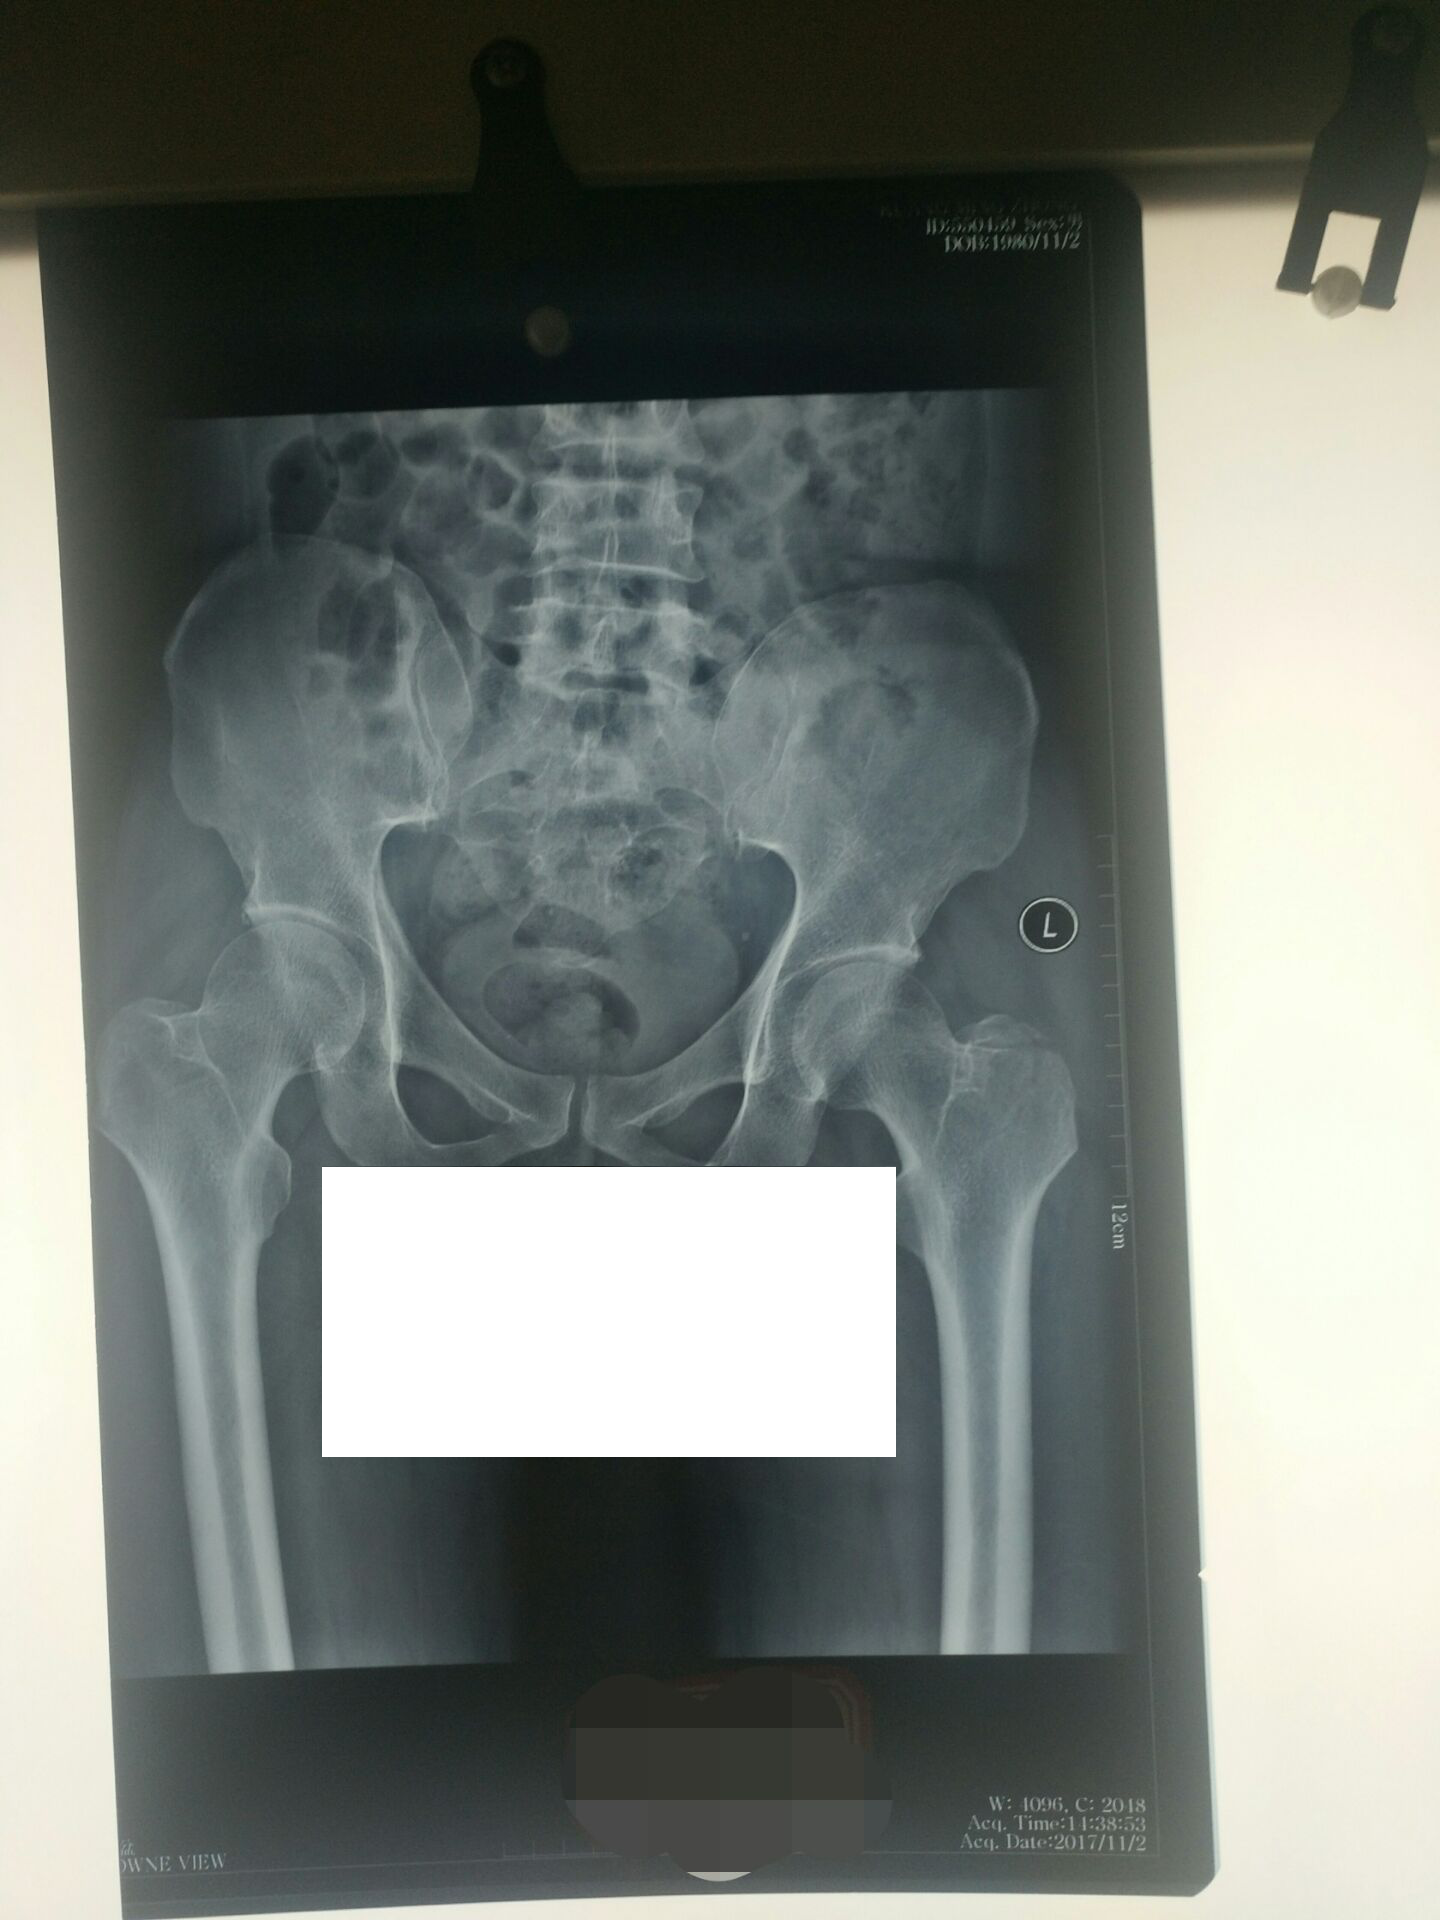

3、复阅高安市人民医院DR(550459、559863等):左股骨大转子骨折。

XX人民医院病历摘要(住院号:0109045):况某于2017年11月01日因外伤致左髋部肿痛、活动受限1小时余入院,入院时患者神志清楚,左髋部稍肿胀,左髋部压痛明显,肢体纵向叩击痛明显,患肢运动功能明显受限。DX及CT提示左股骨大转子骨折。诊断:1)左股骨大转子骨折;2)全身多处软组织挫伤。入院后完善相关检查,予以消肿止痛、对症等处理。 2017年12月23日出院。出院诊断同入院诊断。